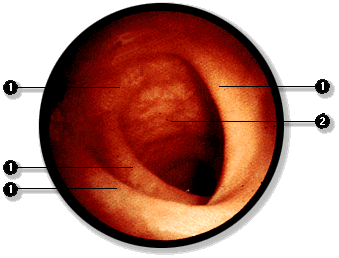

En el sujeto vivo el estómago, el duodeno y la porción superior del yeyuno puden ser explorados directamente mediante la técnica de endoscopía.

En este examen se introduce por vía oral, el fibroscopio, el cual es deslizado a través de la faringe y esófago hacia el estómago y el instestino. A través del instrumento es posible realizar cauterizaciones de puntos sangrantes y tomar muestras de mucosa. El examen que incluye todas estas vísceras: esófago, estómago, intestino delgado se denomina panendoscopía.